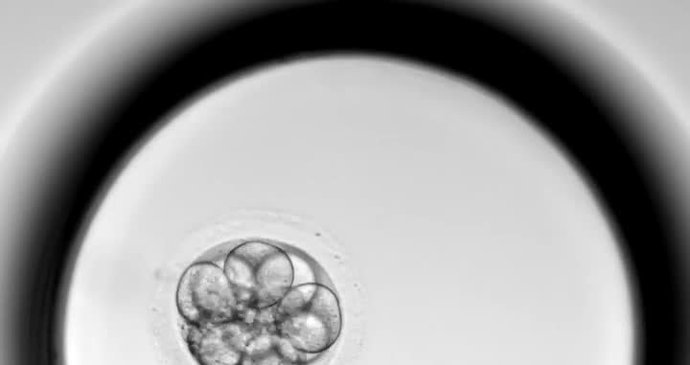

Děti narozené z umělého oplodnění jsou vystaveny většímu výskytu nádorových onemocnění. To údajně vyplývá z určitých studií. Blesk zjišťoval, kde je pravda a o jakých číslech se hovoří. Je to riziko opravdu vysoké? Je situace alarmující? A měla by centra asistované reprodukce varovat před tímto rizikem?

Podle vedoucího lékaře Miloše Černého je třeba hned v úvodu říci, že nádorová onemocnění v dětském věku jsou opravdu vzácná a jejich výskyt je opravdu ojedinělý, bohužel ale je. Je tedy pravdou, že děti počaté metodou IVF mají mírně zvýšené riziko některých nádorových onemocnění, jako jsou retinoblastom, neuroblastom a leukémie?

„To jsou studie ze severní Evropy, které říkají, že je tam u těch dětí po IVF ta šance o něco zvýšená, ale ta čísla jsou tak malá, že ty studie vyšly tak, že z 10 000 to nevyšlo jako 10, ale 14 nebo 15, takže ono opravdu těžko pak dělat takovou studii a závěr, když každé dítě udělá velký rozdíl u toho,“ uklidňuje doktor Černý a hovoří, že situace rozhodně není znepokojující.

„Když by ta čísla byla desetinásobná, tak se to dá nějak opravdu uzavřít a říct, že to tak je, ale tady místo 10 dětí z 10 000 se ukázalo, že to mělo 15 dětí z 10 000, tak myslím, že z toho zase nejde dělat jako závěr tím, že by tam byl jednoznačně zásadně zvýšený výskyt nádorů,“ dodal lékař.

„Těch možností je samozřejmě víc. Může to být způsobeno manipulací s vajíčkem, se spermií, přece jenom to otěhotnění není přirozené. Většinou se vybere obrovským zvětšením mikroskopům hezká spermie, taková, která se hýbe hezky rovně, má normální tvar, normální velikost a tam tu vlastně embryolog vezme do tenké jehličky a do vajíčka píchne přímo tu spermii, takže to není přirozené početí,“ vysvětluje Černý a dodává, že dalšími příčinami mohou být například mikromanipulační metody nebo věk párů.